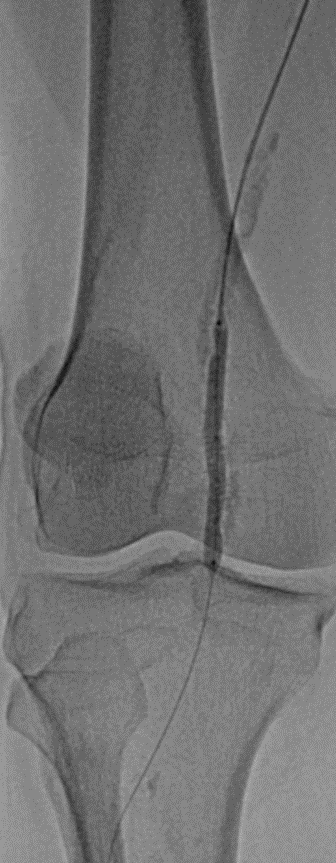

随后使用LiqMagic?P18外周血管内冲击波导管进行钙化斑块的压裂。根据血管尺寸,团队选择了4.0*60mm和5.0*60mm两个规格在4atm压力下逐段扩张整段病变,共进行了6个周期的冲击波治疗,将冲击波球囊加压至12atm显示病变狭窄解除,均匀扩开,保压1min后造影结果显示血流恢复通畅,钙化部位的残余狭窄明显改善。

▲首次冲击波球囊扩张后造影

▲再次冲击波球囊扩张后造影

最后使用心脉医疗?Reewarm?PTX 5*220mm药物球囊扩张导管扩张3min,再次造影显示原闭塞段血流通畅,无限流性夹层,血管形态良好,胫前动脉、腓动脉血流流速较前明显改善。